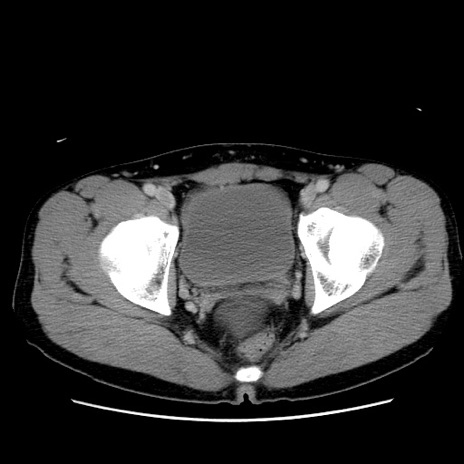

症例36(横断像)

【症例】20歳代 男性

【主訴】心窩部痛

【現病歴】今朝より上腹部痛あり。一旦軽快していたが再度出現したため救急要請。昨日夕に白身の魚を含む刺身を食べた。

【身体所見】BP 136/89mmHg、HR 74/min、BT 37.0℃、腹部:膨満、軟、心窩部に圧痛あり。反跳痛なし、筋性防御なし、腸雑音やや亢進あり。

【データ】WBC 17700、CRP 0.48